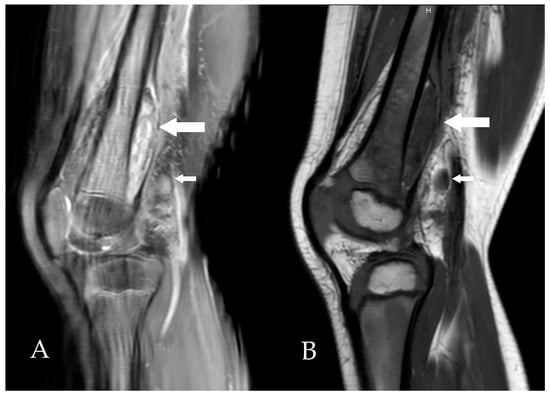

The collection could not be aspirated because of its deep location and anatomical inaccessibility. Clindamycin (40 mg/kg/day in 3 doses) was initiated for a total duration of 7 weeks. At one-month follow-up, the outcome was favorable, with complete resolution of the mobility restriction and control ultrasound showing a moderate decrease in the abscess size (Figure 2).

Figure 2. Sagittal ultrasound scans obtained at diagnosis (A), two weeks later (B), and three months after treatment initiation (C), showing progressive regression of the subperiosteal collection (between calipers).